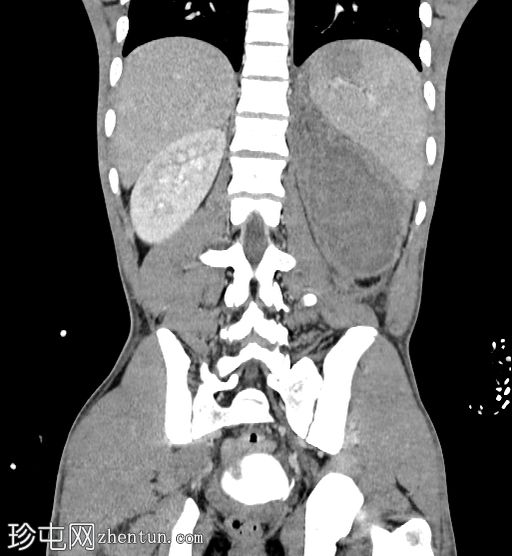

冠状位增强扫描(门静脉期)

左肾包膜下(毗邻肾后包膜)可见一相对高密度、无强化的积液(平扫时HU=70),包绕左肾。

左肾下极可见肾实质不连续(>1 cm,未累及集合系统),提示

肾脏

撕裂伤部位。

左肾受巨大血肿压迫;但可见肾实质强化正常,造影剂排泄至集合系统。未见造影剂外渗。

III级肾损伤的特征(撕裂伤>1厘米,未累及集合系统,血肿局限于肾周筋膜内)